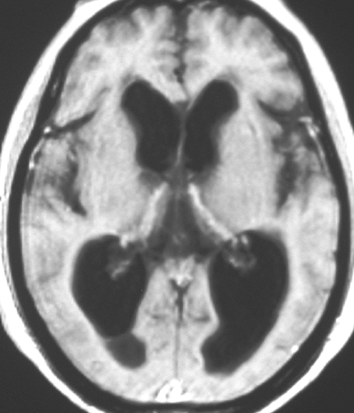

上の写真が小さな聴神経腫瘍とかなり進行した水頭症です。80歳近い男性の患者さんが認知症(痴呆)とまちがえられていました。おしっこをもらしたり,歩行が不安定でよたよたしていました。これは小さな15mmくらいの聴神経腫瘍があるために水頭症になってしまったから起こった症状です。ですから,脳の中に溜った水をお腹までチューブで流すシャント手術という簡単な手術で認知症も歩行障害も治りました。もちろんこの小さな腫瘍は治療する必要がないので何もしないでほっておきました。おそらくかつてはもっと大きな腫瘍だったのでしょう。